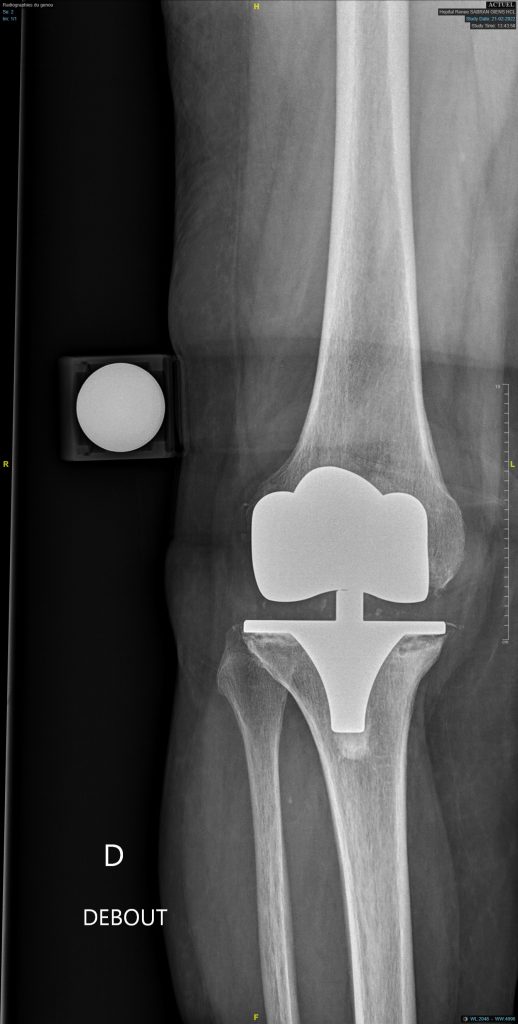

Certaines problématiques peuvent nécessiter une chirurgie de révision prothétique, c’est-à-dire, un changement d’un ou des implants. Dans les causes les plus fréquentes, on peut noter :

• Une usure des composants pouvant être ou non responsable d’une lyse osseuse et d’un descellement des implants.

• Un descellement

La chirurgie de révision ou de reprise varie d’un cas à l’autre avec la nécessité de changer en fonction des cas un seul implant, ou l’ensemble de la prothèse.

Les implants utilisés pour ce type de chirurgie doivent une bonne tenue malgré les pertes de substance osseuse. L’utilisation de quilles longues, de cales ou de cônes est souvent nécessaire.

Avant d’envisager une chirurgie de reprise, il est souvent nécessaire de réaliser un bilan complet permettant d’éliminer une infection, d’évaluer le stock osseux et la position des implants (bilan biologique +- ponction; scanner ; scintigraphie ; clichés en stress).